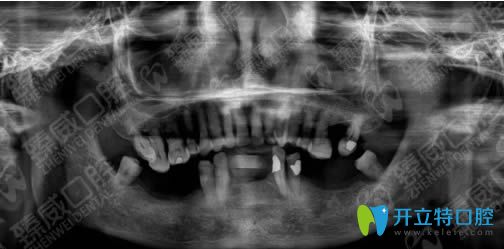

<下圖是我種植牙前的口腔CT片>:

我的下顎牙床已萎縮,上頜牙還都能要硬東西,但下頜牙松動的難以咀嚼食物,只能吃一些稀爛的飯菜......魏東醫(yī)生考慮到我身體耐力差等身體因素,為我定制下頜all-on-4即拔即種修復(fù)方案,說只需要4個種植體即可恢復(fù)半口牙。